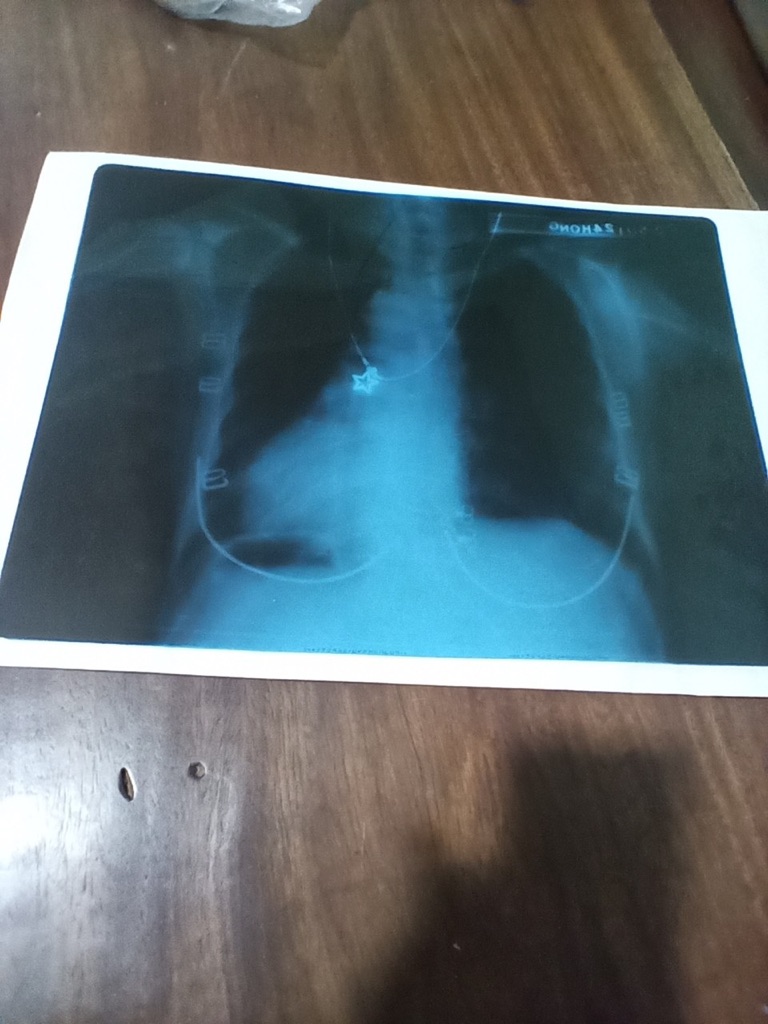

Bác sĩ cho em hỏi mẹ em bị đau họng có đàm , lâu lâu ho 1 2 cái , bị nay 2 tuần hơn chưa hết chị bớt thôi , có uống thuốc đủ , nhưng mỗi lần ho là đau ngực nhẹ , sau mấy ngày ngực đau nhẹ kiểu rim rim ngực , mới 3 bữa trc mẹ em cảm thấy cổ vướng vướng thì khạc ra cục máu đông , có đi khám chụp x quang phổi thì có đốm trắng ở phổi ạ , nay 4 ngày uống thuốc chỗ chụp x quang cho 4 bữa nhưng ngực vẫn còn nhức rim rim nhẹ , mệt mỏi trong người Không biết mẹ em bị sao ạ mong bs giúp em :((